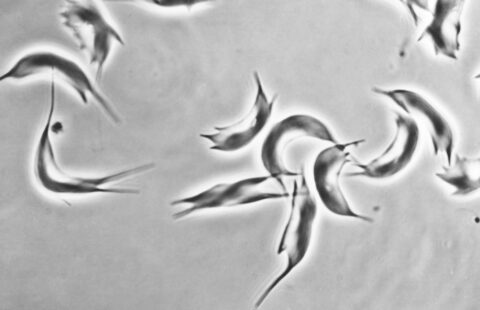

©Inserm/Soichot, Julien